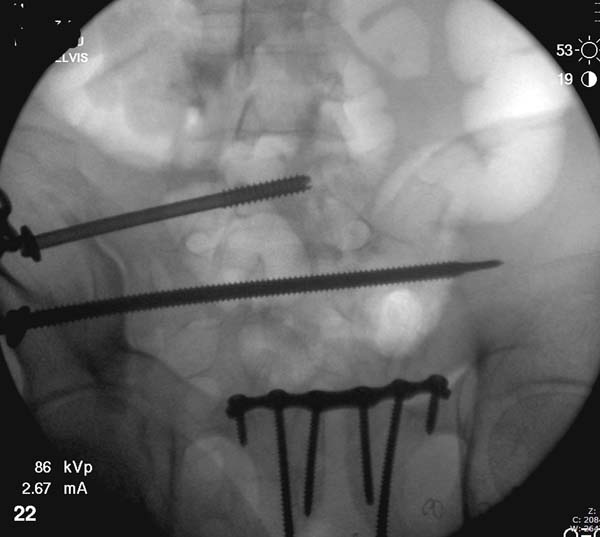

Но вам повезло, двумя винтами смогли зацепить и репонировать

переломо-вывих. Обычно такие переломы надо фиксировать спереди или сзади

пластиной или шурупом, т.е. создать дополнительную стабильность крыла,

кроме  перкутанной фиксации.

Здесь примеры фиксации с различными вариантами.... .